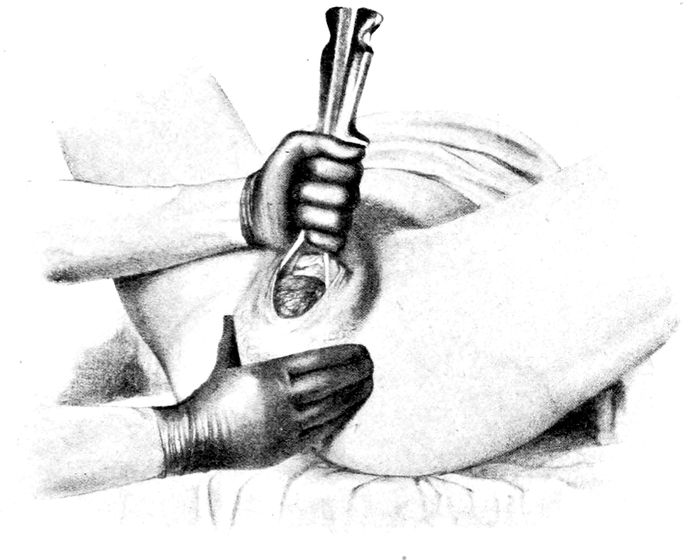

187 |

| 76. |

187 |